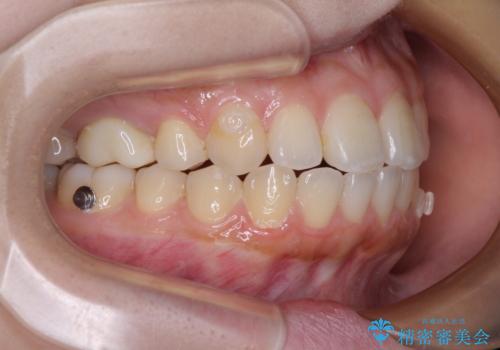

再矯正 開咬に後戻りした歯列をインビザラインで改善

- 矯正治療の後戻りを気にして来院された患者様です。

デコボコと上下前歯の隙間が気になるものの、しっかりと治療をしたいという意思はないとのことで、インビザラインの中でもアライナー数に制約のあるライトパッケージを用いて、治療できる範囲まで歯列を改善していくこととしました。

インビザラインは前歯部の開咬に効果的であることが多く、ライトパッケージにもかかわらず、十分満足のいく仕上がりとなりました。